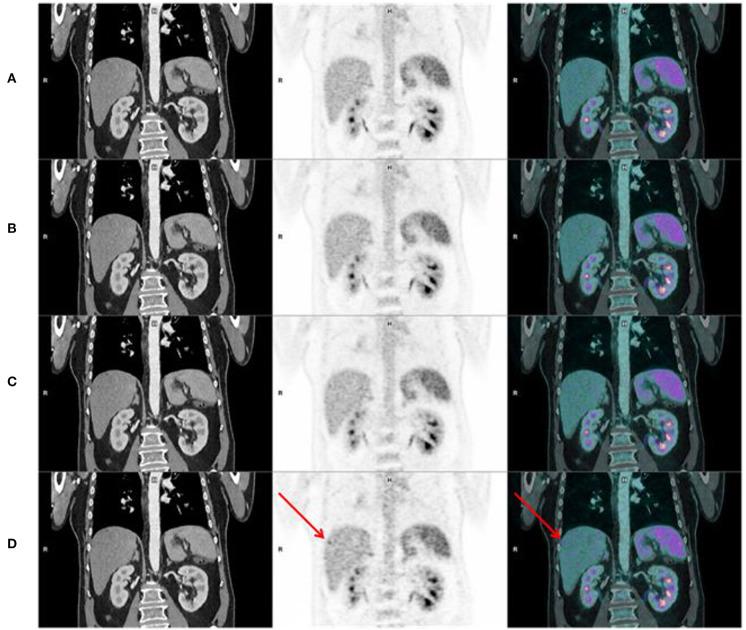

The aim of this study was to assess image quality and lesion detectability acquired with a digital Positron Emission Tomography/Computed Tomography (PET/CT) Siemens Biograph Vision 600 system. Consecutive patients who underwent a FDG PET/CT during the first week of use of a digital PET/CT (Siemens Biograph Vision 600) at the nuclear medicine department of the university hospital of Brest were analyzed. PET were realized using list mode acquisition. For all patients, 4 datasets were reconstructed. We determined, according to phantom measurements, an equivalent time acquisition/reconstruction parameters pair of the digital PET/CT corresponding to an analog PET/CT image quality ("analog-like") as reference dataset. We compared the reference dataset with 3 others digital PET/CT reconstruction parameters, allowing a decrease of emission duration: 60, 90, and 120 s per bed position. Three nuclear medicine physicians evaluated independently, for each dataset, overall image quality [Maximal Intensity Projection (MIP), noise, sharpness] using a 4-point scale. Physicians assessed also lesion detection capability by reporting new visible lesions on each digital datasets with their confidence level in comparison with analog-like dataset. Ninety-eight patients were analyzed. Image quality of MIP (IQ), sharpness (IQ), and noise (IQ) of all digital datasets (60, 90, and 120 s) were better than those evaluated with analog-like reconstruction. Moreover, digital PET/CT system improved IQ, IQ, and IQ whatever the BMI. Lesion detection capability and confidence level were higher for 60, 90, 120 s per bed position, respectively, than for analog-like images. Our study demonstrated an improvement of image quality and lesion detectability with a digital PET/CT system.

摘要